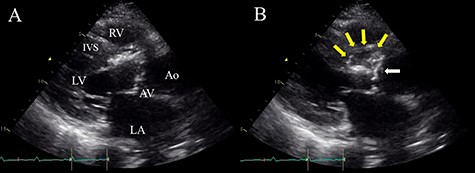

A 58-year-old man with a history of angina pectoris and diabetes mellitus was admitted to our medical center because of high-grade fever and progressive cough for 4 weeks. On examination, his temperature was 38.5°C, and a grade 3/6 systolic murmur was audible at the right sternal border in the second intercostal space. Laboratory findings showed leukocytosis (white blood cell count (WBC), 18 310 μ/l), high C-reactive protein (CRP) level (10.8 mg/dl) and a high procalcitonin level (3.17 ng/ml). Streptococcus saccharolyticus was identified from two samples of blood cultures. Initial transthoracic echocardiography (TTE) revealed severe aortic stenosis, with a mean pressure gradient of 65 mmHg, due to a calcified bicuspid aortic valve and small vegetation attached to the aortic valve. Magnetic resonance imaging of the brain revealed multiple small acute cerebral infarctions. We initially started intensive intravenous antibiotic therapy (sulbactam/ampicillin: 12 g/day, gentamycin: 120 mg/day) based on the diagnosis of infective endocarditis complicated by acute cerebral infarctions. His fever subsided immediately, and the WBC and CRP levels returned to the normal range. However, repeat TTE revealed an aortic annular abscess below the right coronary cusp extending into the IVS (Fig. 1A and B). Therefore, we decided to perform emergent surgery, including aortic valve replacement and radical debridement of the aortic annulus and IVS, on Day 34 after admission.

Preoperative TTE (parasternal long-axis view) showing vegetation on the aortic valve (white arrow) and aortic annular abscess extending to the IVS (yellow arrows); (A) end-systolic phase; (B) end-diastolic phase; LV, left ventricle; RV, right ventricle; LA, left atrium; AV, aortic valve; Ao, ascending aorta.